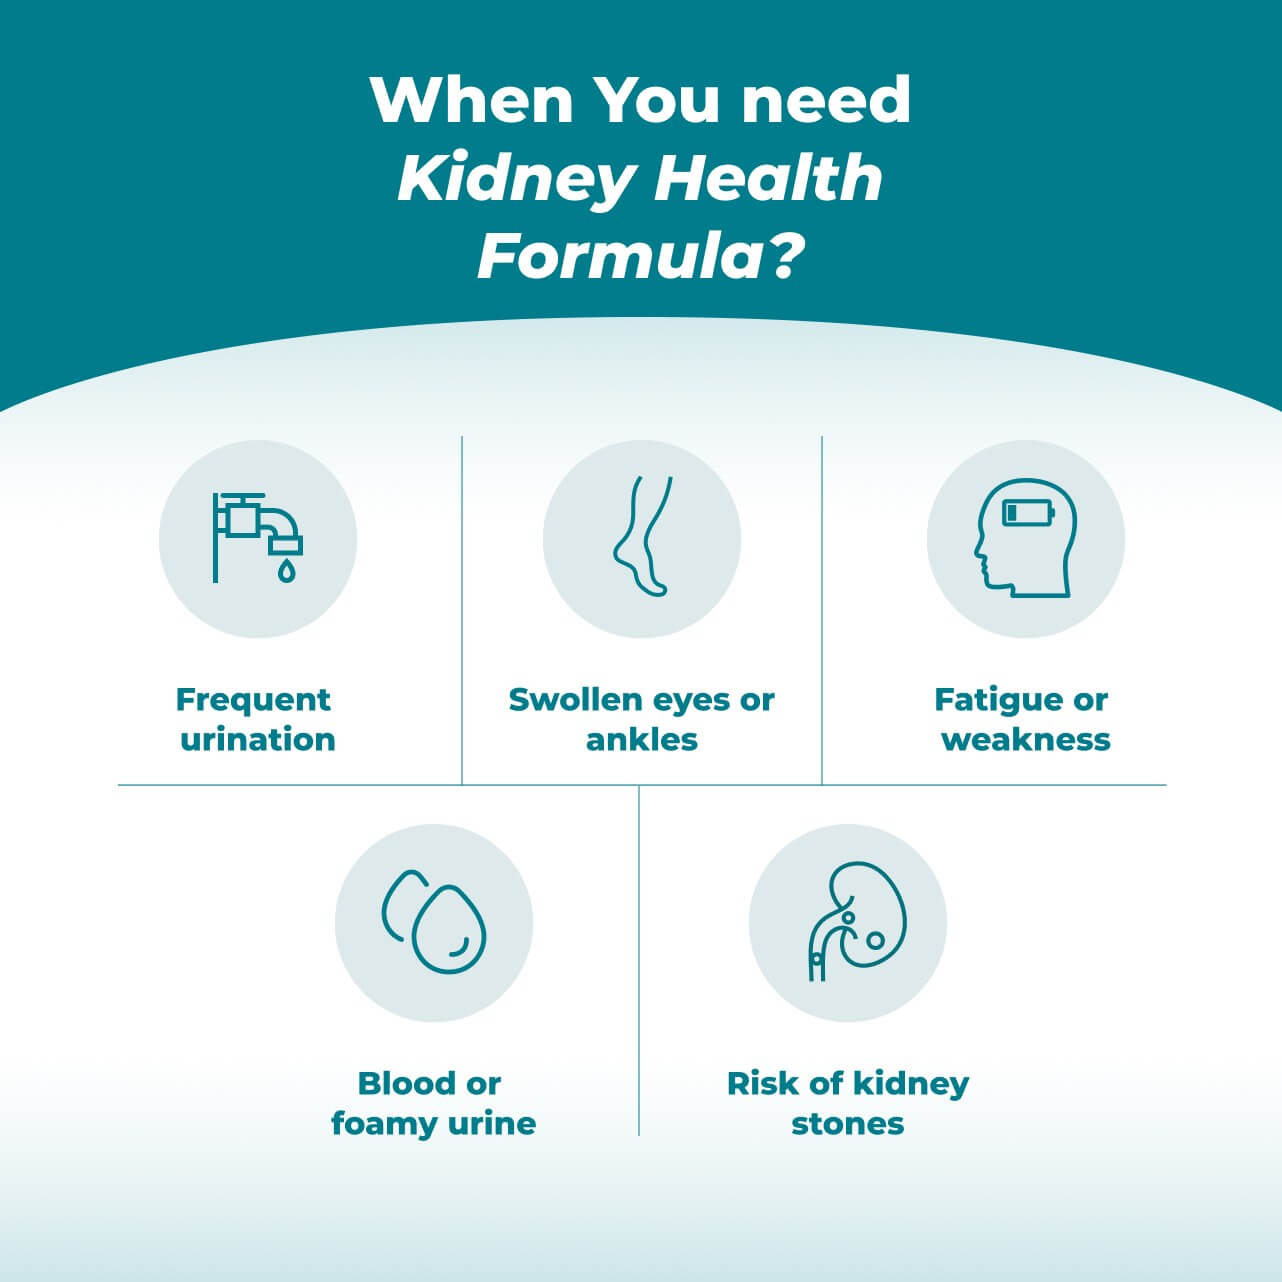

Reduced kidney function can make it hard to concentrate, sleep, and feel weak or tired. You may get puffy eyes, swollen ankles/feet, muscle cramping, or itchy skin. And you might have blood in the urine, foamy urine, or urinating more often, especially at night.

When kidney performance falters, the impact is almost immediate.

When kidney performance falters, the impact is almost immediate.

Nearly all your internal organs are affected.